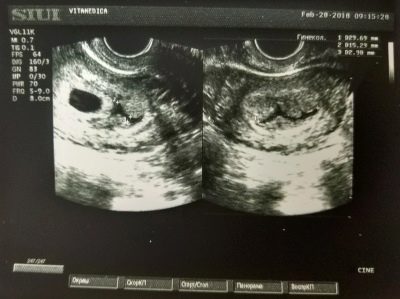

Ультразвуковое обследование дает довольно приблизительное представление о составе вод, прозрачности. До конца первого триместра обычно воды анэхогенные, в них нет эховзвесей. Со второго триместра может в норме обнаруживаться эхопозитивная мелкодисперсная взвесь, которая и является, по сути, первыми частицами жизнедеятельности малыша.

На этих сроках взвеси определяются только очень чувствительными сканерами, их количество невелико, а потому говорят об их единичном присутствии в поле зрения. Эхопозитивная гиперэхогенная взвесь может присутствовать в водах с конца второго триместра, чем больше срок беременности, тем ее количество больше. Если обнаруживается слишком много взвеси, то говорят о перенашивании беременности, но такое обычно уже наблюдается после того, как предполагаемый срок родов давно истек, а роды еще не наступили.

Если эховзвесь крупнодисперсная, хлопьевидная, то это чаще всего означает, что в водах присутствуют патологические примеси, например, меконий. Но точно установить это ультразвуковое обследование не позволяет. Оно определяет лишь факт присутствия, а вот детали помогают выяснить другие методы.